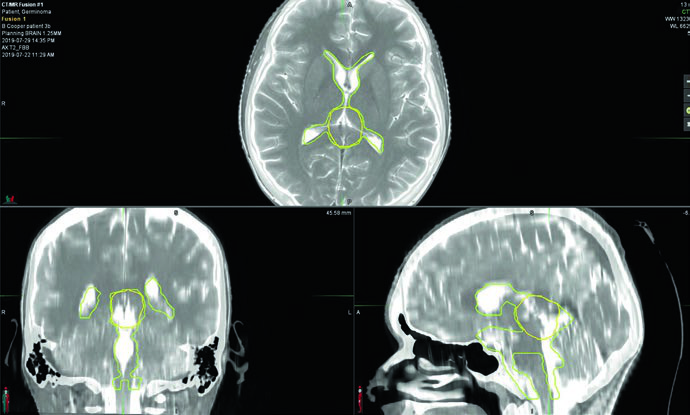

Germinoma puro: irradiación ventricular y boost

La planificación exige RM pre y posoperatoria de 1–3 mm de espesor de corte cubriendo cerebro y columna. Los marcadores séricos y en LCR de beta-hCG y alfa-fetoproteína son fundamentales para descartar componente no germinomatoso: cualquier elevación de AFP reclasifica el tumor como NGGCT. En el protocolo ACNS 1123, los pacientes con beta-hCG sérica o en LCR superior a 100 mIU/mL fueron tratados como NGGCT.

Los germinomas bifocales — compromiso simultáneo supraselar y pineal — se tratan como enfermedad localizada con irradiación ventricular total seguida de boost de campo involucrado. El volumen blanco incluye el tumor prequimioterapia, cualquier enfermedad residual y todo el sistema ventricular. Delinear la enfermedad prequimioterapia en el momento de la planificación inicial es crítico, porque el volumen de boost frecuentemente se extiende más allá de los límites ventriculares normales.

El boost CTV se define como GTV prequimioterapia + 1 a 1,5 cm. La inclusión de la cisterna prepontina es opcional, pero debe considerarse en pacientes sometidos a ventriculostomía o con tumores supraselares voluminosos.